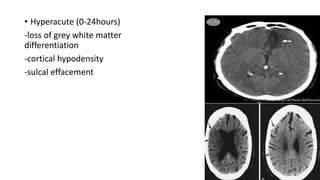

• Hyperacute (0-24hours)

-loss of grey white matter

differentiation

-cortical hypodensity

-sulcal effacement